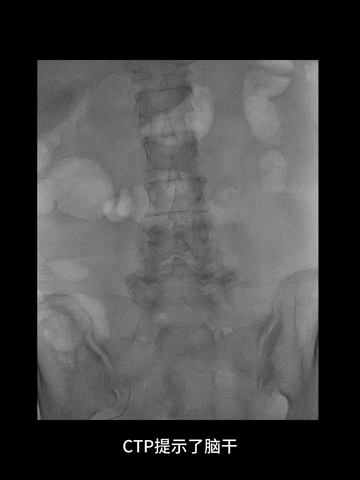

CTP:脑干和小脑广泛TTP延长,但未见明显CBV和CBF严重降低区域。